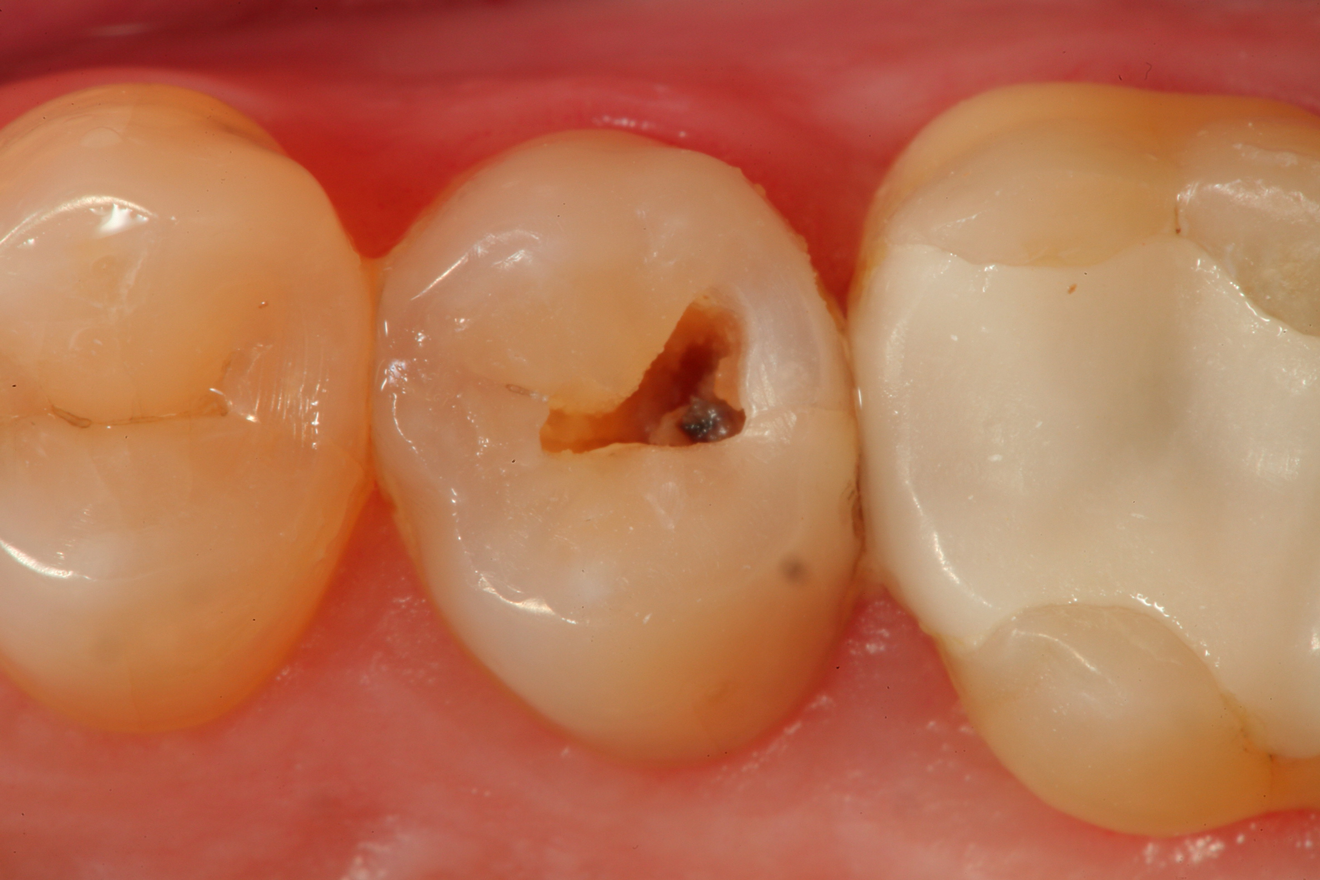

Fig 10. A preoperative occlusal view of tooth Nos. 18 and 19 with composite restorations that are exhibiting marginal breakdown.

Figure 10

A 32 year-old female patientpresented with old composite restorations in tooth Nos. 18 and 19 that exhibited marginal leakage with potential for recurrent decay (Figure 10).  After excavation, both teeth had deep decay beyond the extent of the restorative material, with tooth No. 19 having a "pinpoint" carious exposure of the pulp chamber (Figure 11).  Figure 12 is a diagrammatic representation of the therapeutics that were used after removal of infected dentin and control of the bleeding from the pulp exposure.  A pulp protectant/liner that is indicated for use on a direct pulp exposure (TheraCal LC, Bisco Dental Products) was placed directly on the exposed area and light cured.  Both preparations were then filled with a bioactive dentin replacement (TheraBase, Bisco Dental Products) to a point just apical to the dentoenamel junction (Figure 13).  Selective etch protocol was then used, etching the enamel (Select Etch HV, Bisco Dental Products) for 15 seconds (Figure 14), then rinsing with water and drying.  Next, a universal bonding agent (All-Bond Universal, Bisco Dental Products) was placed, air thinned, and light cured (Figure 15).  Figure 16 is an occlusal view of the completed restorations.  Both teeth are planned to be followed and radiographed periodically to ensure that the pulps are responding favorably.